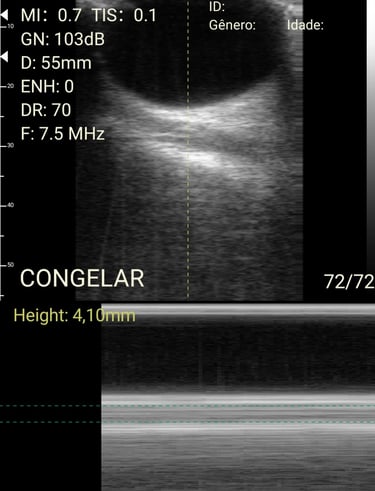

Análises detalhadas de procedimentos com o método HUGO.